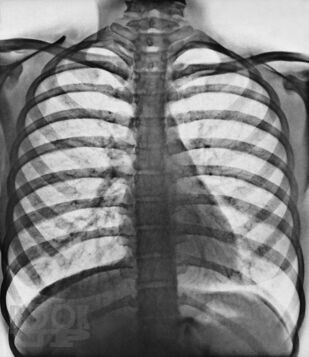

Переработанное и дополненное 3-томное издание «Sobotta. Атлас анатомии человека» является современным учебным пособием. Новое издание атласа отличается от предыдущих клинической направленностью преподавания анатомии: приведено большое количество клинических наблюдений, подтверждающих значение глубоких фундаментальных знаний анатомии при диагностике и лечении различных патологий. Это в полной мере соответствует современным требованиям, предъявляемым к медицинскому образованию, и адаптировано к новым образовательным стандартам. Атлас структурирован по региональному принципу, что соответствует темам учебных сертификационных циклов. Первый том включает разделы общей анатомии, а также подробно иллюстрирует строение костей, их соединений и мышц туловища и конечностей. Упрощенные схемы вводного характера и общие обзоры помогают понять более сложные рисунки и связи. Второй том посвящен анатомии внутренних органов грудной, брюшной полостей и органов таза. В третьем томе представлена анатомия органов головы, шеи, большой раздел посвящен нейроанатомии. Новое издание содержит высококачественные иллюстрации, дополненные подробными подрисуночными подписями. Оригинальные рисунки сопровождаются современными изображениями, полученными с помощью компьютерной и магнитно-резонансной томографии, ультразвуковых и эндоскопических методов исследования, а также интраоперационными цветными фотографиями внутренних органов и т.д. К атласу прилагаются таблицы, содержащие краткую систематизированную информацию об анатомии и о функциях мышц, суставов и об их иннервации. Использование в атласе трехъязычной терминологии повышает интерес к нему со стороны иностранных студентов, обучающихся медицине в России.